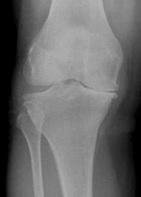

The x-ray above shows reduced joint space between the tibia and the femur in the medial tibio-femoral compartment.

WHAT DOES THE X-RAY SHOW?

When a surgeon looks at your x-rays he is looking for reduced joint space (thinning of the cartilage covering), extra new bone formation (osteophytes), bone cyst formation and thickening of the bone underneath the joint surface (subchondral sclerosis). These are all radiological signs of osteoarthritis. He will also be looking at the quality of your bone, the alignment of your leg and for any evidence of bone loss in severe deformities.